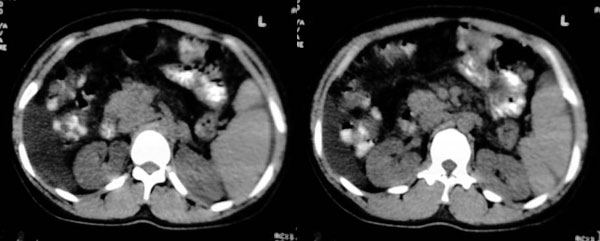

患者:女,43岁,自觉全身肿胀8个多月。b超提示:肝硬化、腹水,胆囊炎。胰、脾、肾未见明显异常。

肝脏形态不正常,比例失调,肝裂增宽,应该是肝硬化、腹水、脾脏稍大。

肝脏体积变小,左右比例失调,右肝变小较剧,脾脏增厚,腹水征象明显考虑肝硬化、腹水

大家好,还有就是她的胆囊在哪?那肝右前间隙液体内环状稍高密度是什么,又为什么壁欠光滑.请大家再帮忙看看.

肝右前间隙液体内环状稍高密度,请查附件看有没有肿瘤。

肝右前间隙液体内环状稍高密度,不会就是胆囊吧?

另:肝前缘液体内环形影是漂浮的肠管.

支持肝硬化、腹水、脾大。,另腹水内漂浮的圆形阴影考虑:1 胆囊 2 大量腹水后继发感染形成脓肿。

支持楼上各位老师的讨论,但还需要提醒楼主注意食管腹部,有可能是食道癌。再者就要怀疑是食管周围的病变,考虑是肿大的淋巴结。

肝脏体积缩小,左右肝比例失调,轮廓不规整,肝裂增宽,肝周见新月形液性密度影,脾脏增厚.应诊断为肝硬化,腹水,脾大.